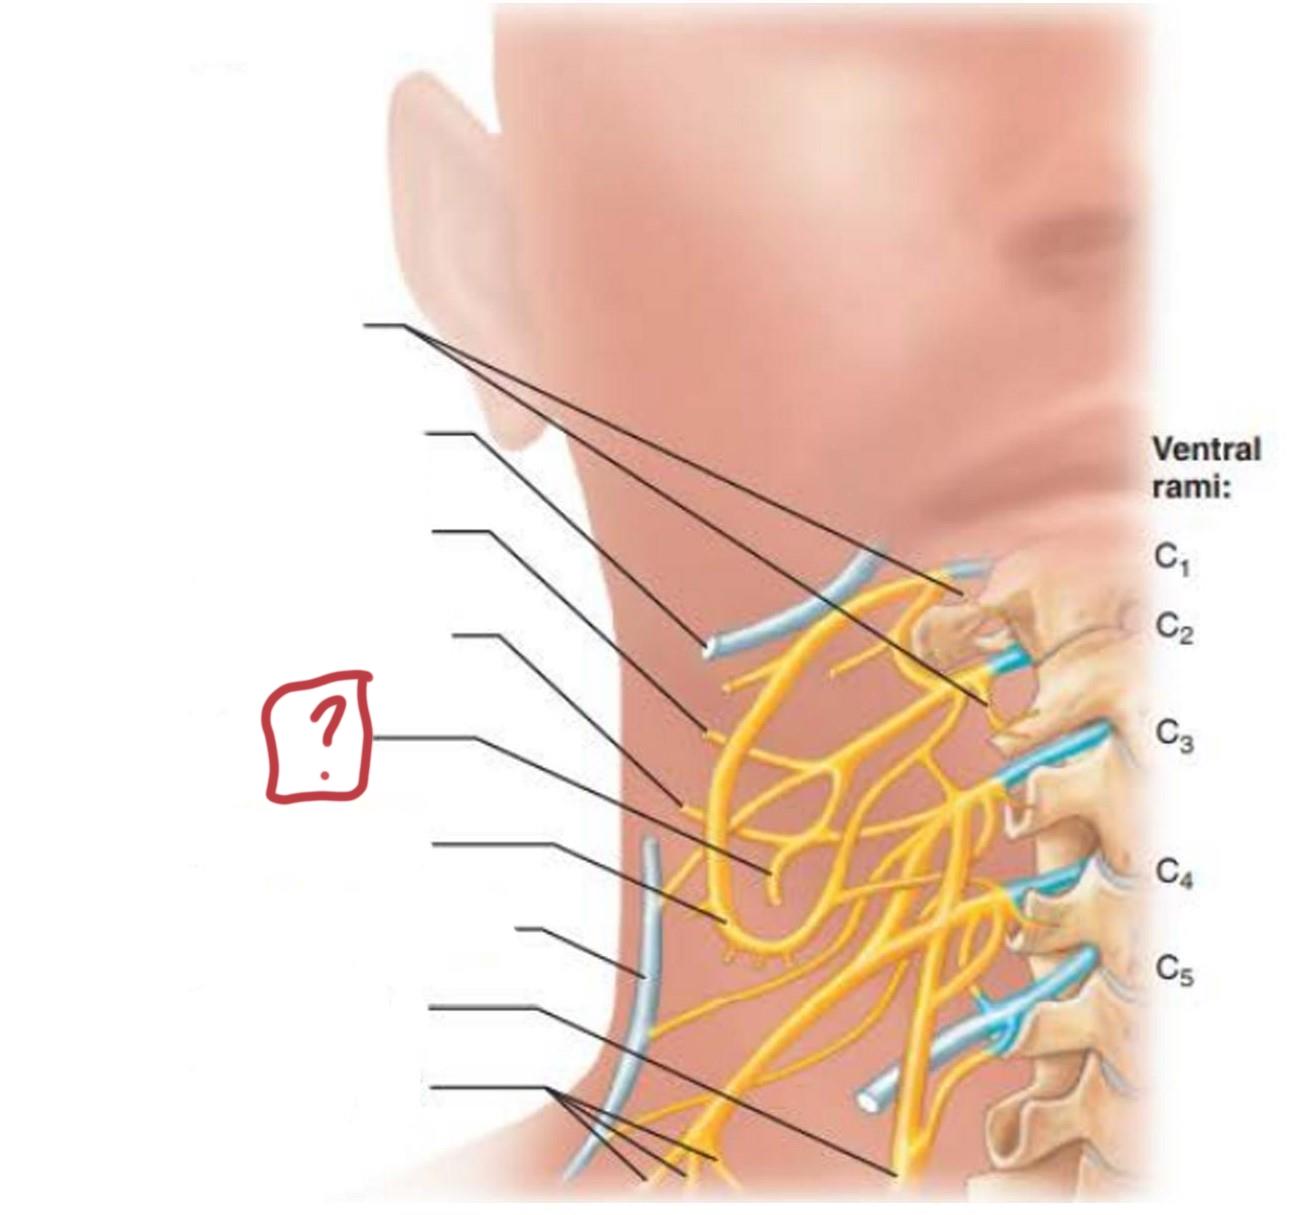

cervical plexus

C1-C4

segmental branches

hypoglossal nerve (12)

lesser occipital nerve

greater auricular nerve

transverse cervical nerve

ansa cervicalis

accessory nerve (11)

phrenic nerve

supraclavicular nerves